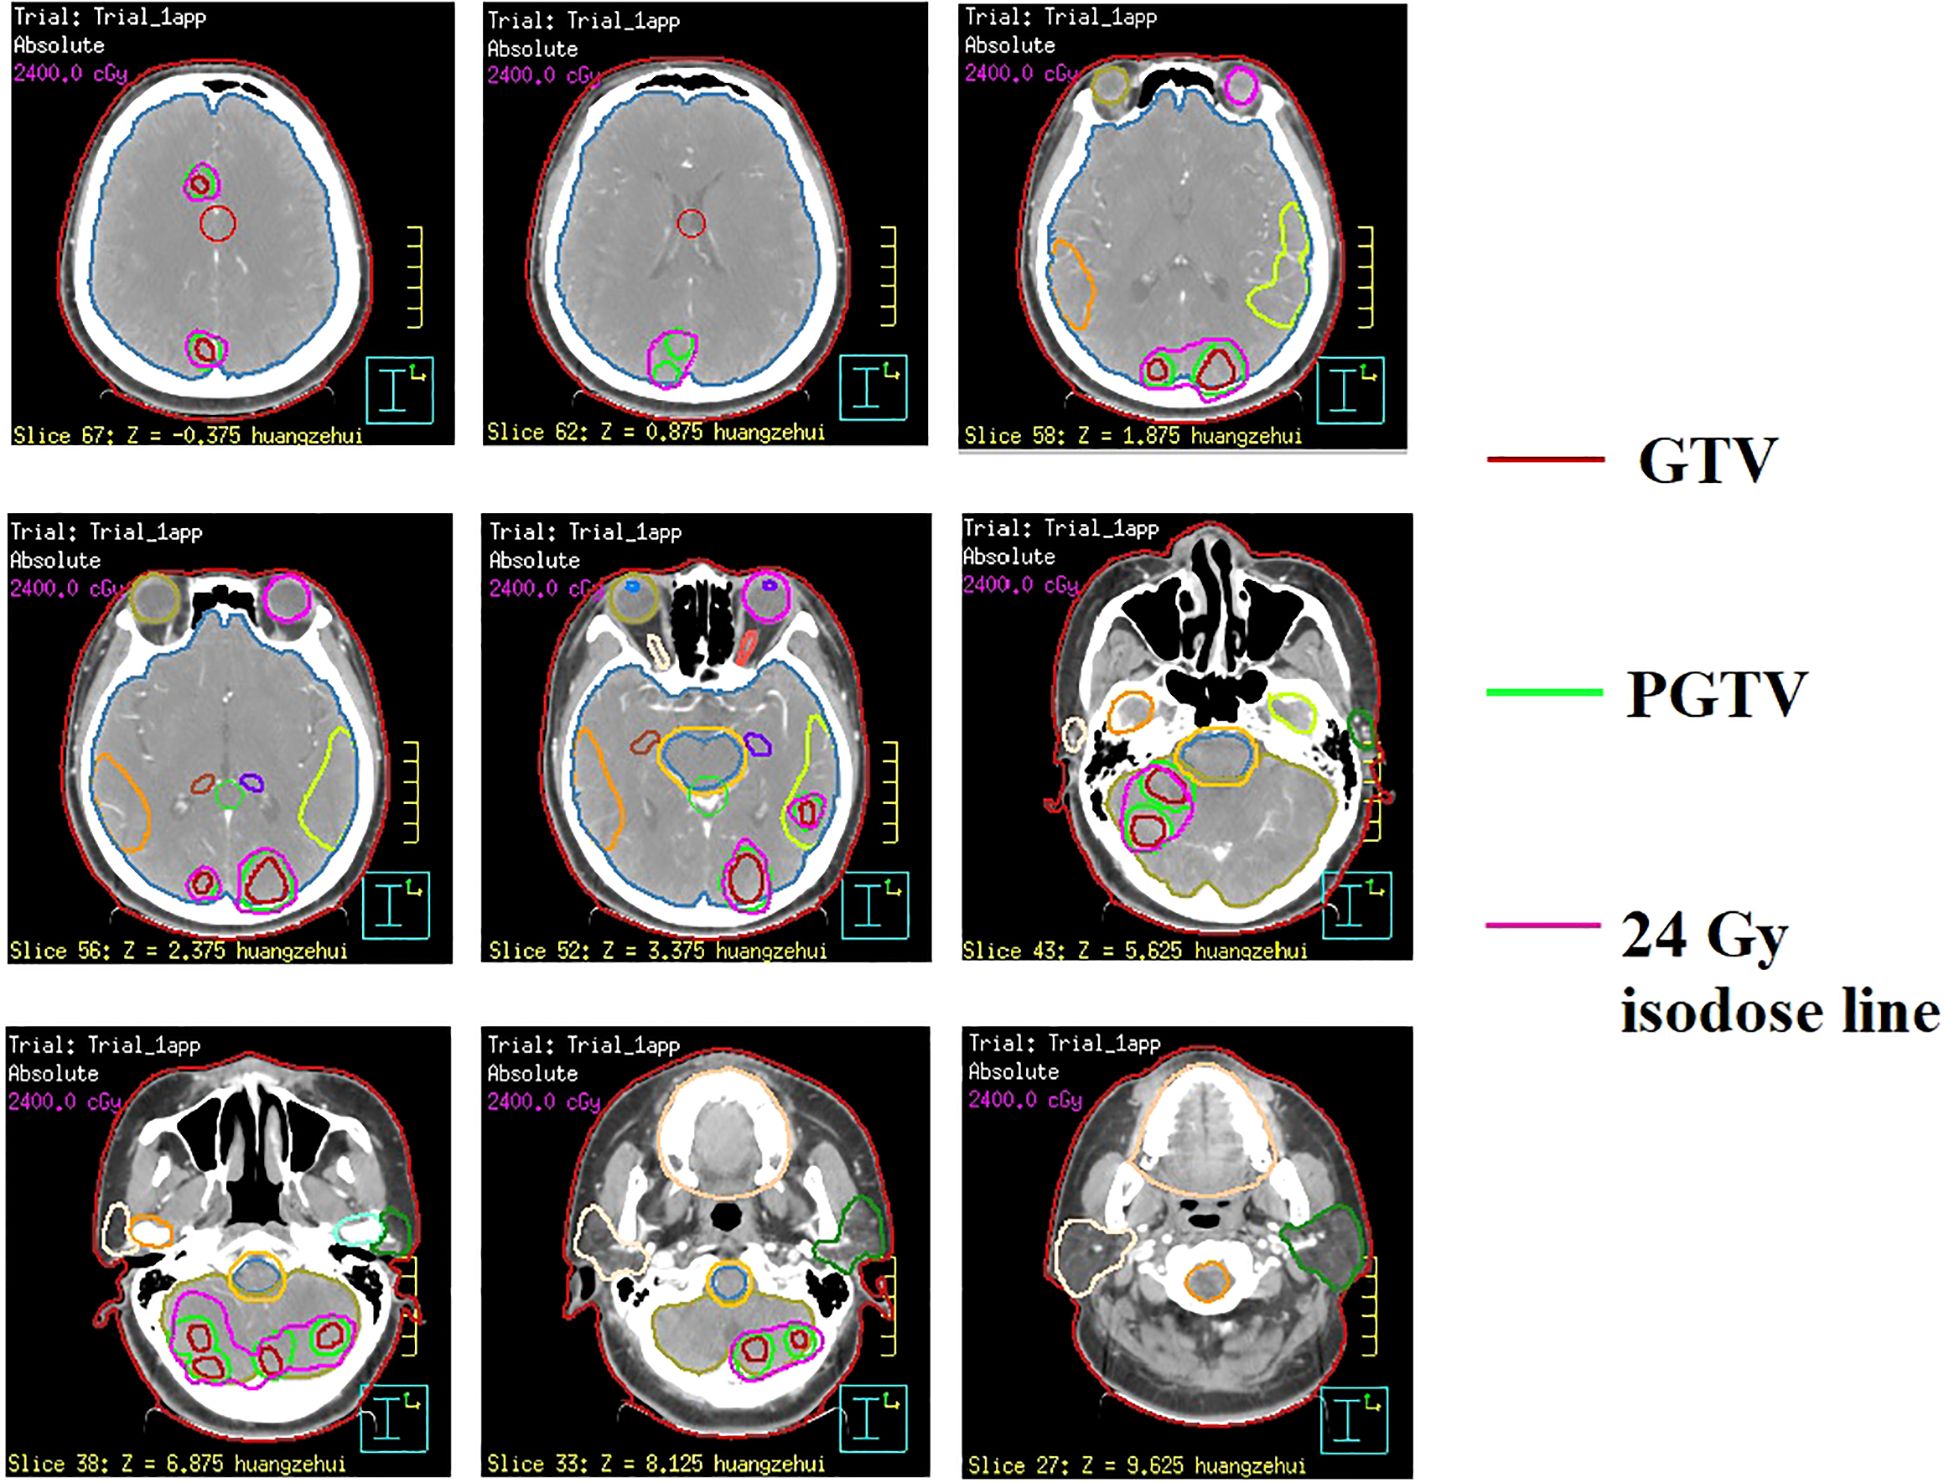

In February 2022, the patient presented with mild dizziness and unsteady gait. Head magnetic resonance imaging (MRI) revealed multiple brain metastases in the bilateral frontal, parietal, temporal, and occipital lobes, as well as in the cerebellar hemisphere, without evidence of extracranial tumor recurrence. Based on these clinical findings, the patient received WBRT on February 22, 2022, utilizing a Varian Clinac 6EX linear accelerator with 6MV photon beams. Radiation treatment was administered using a single-isocenter technique with coplanar, parallel-opposed lateral beams to ensure comprehensive target coverage (PTV 30 Gy/10 F/2 W). Additionally, sequential integrated boost radiation therapy (SEB) was administered on March 10, 2022 (IMRT, PTV 24 Gy/12 F/3 W). The cumulative equivalent dose in 2 Gy fractions (EQD2; α/β = 3) to organs at risk (OARs) was quantified as follows: brainstem (51.2 Gy), optic chiasm (left: 40.9 Gy; right: 41.3 Gy), lens (left: 5.3 Gy; right: 5.2 Gy), and globe (left: 4.18 Gy; right: 3.6 Gy). All dose parameters remained within established clinical tolerance limits. Owing to the extensive intracranial metastatic burden and the necessity for comprehensive target coverage, strict adherence to RTOG 0933 hippocampal dose constraints was not feasible. Quantitative dosimetry demonstrated mean/maximum hippocampal doses of 3.8 Gy/43.8 Gy (left) and 3.9 Gy/45.5 Gy (right). Following multidisciplinary risk-benefit evaluation, we implemented a clinically justified dose optimization strategy that prioritized tumor control while minimizing neurocognitive risks. Refer to Figure 1 for the diagram of the radiotherapy target area. Following this treatment regimen, the patient completed four cycles of adjuvant chemotherapy (cyclophosphamide 750 mg/m2, ivgtt, d1 + doxorubicin hydrochloride 50 mg/m2, ivgtt, d1 + vincristine 1.4 mg/m2, iv, d1, Q3w). Subsequently, the treatment strategy was adjusted to maintenance therapy using capecitabine (2 g, po, Bid) after achieved partial remission (PR) based on imaging evaluation, as the patient exhibited intolerance towards chemotherapy.

Figure 1. Illustration of radiotherapy target volumes in sequential integrated boost radiation therapy (SEB) at representative CT levels.